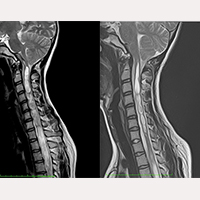

عملية قطع الفيلوم ترمينالي عند مرضى أجروا عملية قطع القحف القفوي

إبتداءا من ٢٠ أكتوبر ١٩٩٣ حتى نوفمبر ٢٠١٦ تم التدخل جراحيا بإجراء عملية قطع الفيلوم ترمينالي، بواسطة تطبيق النظام الطبي الفيلوم سيستم®، على أزيد من ١٠٠٠ مريض مصاب بمرض الفيلوم و /أو متلازمة الجر العصبي مع متلازمة أرنولد كيارى النوع الأول، تكهف النخاع و الجنف، و ذلك في تركيبات مختلفة من التشخيص. في معضم الحالات تم التوصل الى تطورات إيجابية مرضية، إلا في خمسة منها ذي مضاعفات بسيطة